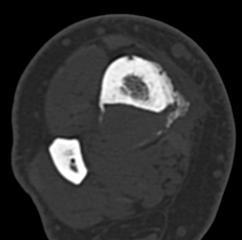

Adamantinome tibial d’aspect agressif avec ostéolyse soufflante rupture corticale et réaction périosté

- Ostéolyse à limites nettes, parfois même condensé avec ostéosclérose périphérique

- Parfois d’aspect plus agressif avec limites floues, rupture corticale et masse des parties molles